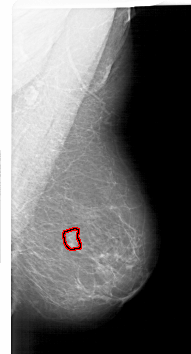

A_1718_1.LEFT_CC

RIGHT_MLO LINES 6016 PIXELS_PER_LINE 3241 BITS_PER_PIXEL 12 RESOLUTION 43.5 OVERLAY

FILE: A_1718_1.RIGHT_MLO.OVERLAY

TOTAL_ABNORMALITIES 1

ABNORMALITY 1

LESION_TYPE MASS SHAPE FOCAL_ASYMMETRIC_DENSITY MARGINS ILL_DEFINED

ASSESSMENT 4

SUBTLETY 4

PATHOLOGY BENIGN

TOTAL_OUTLINES 1

BOUNDARY